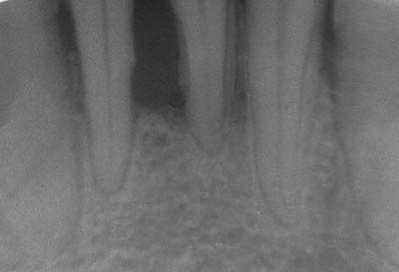

легкая — пародонтальные карманы не более 4 мм, деструкция костной ткани межзубной перегородки до 1/3 длины корней, патологическая подвижность 0-I ст;

средняя — карманы от 4 до 6 мм, деструкция костной ткани перегородок на 1/3-1/2 длины корней, патологическая подвижность І-ІІ ст;

тяжелая — глубина карманов более 6 мм, деструкция костной ткани перегородок более ½ длины корней, патологическая подвижность ІІ-ІІІ ст.

В стадии ремиссии — высокий уровень личной гигиены полости рта, употребление жёсткой, растительной пищи, равномерное участие всех зубов в жевании, своевременное удаление зубных отложений и пломбирование зубов. Для раннего выявления пародонтита необходимо обширное обследование, которое включает сбор сведений, осмотр, зондирование глубины зубодесневых карманов, а также рентгенографию.